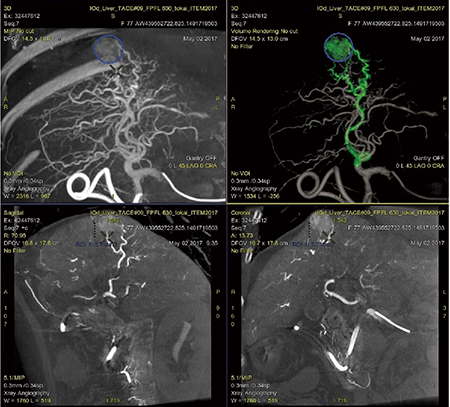

肝動脈化学塞栓療法(以下,TACE)を行うためには,栄養血管が特定されないと手技自体を開始できない。超選択的なTACEをめざして手技自体もさらに複雑化しており,術中に的確で迅速な栄養血管の特定を支援する機能が求められる中で,FlightPlan for Liver(FPFL)が開発された。CBCTデータを基に栄養血管と思われる血管を自動特定し,術者にセカンドオピニオン的に情報提供することで,より効率的なTACEを実現していただくことを目的としている。

FPFLを起動すると,MIPおよびVR画像,そして各断面画像が自動表示される。その後,腫瘍濃染位置をROIで囲みクリック操作すると,栄養血管と思われる信号を自動検出し,VR画像上で緑色に表示する(図4)。血管自体の描出能を妨げることを危惧し,あくまでも色のみを変化させ補助ラインなどは表示しない。かつFPFLによる探索結果とともに,MIPやVR画像ならびに各断面画像を同時表示することにより,術者自身が栄養血管に関して総合的な判断が行えるように画像がレイアウトされている(図5)。

図4 FPFLによる栄養血管の探索結果表示

図5 FPFLの画面レイアウト例

前述のMotion FreezeがFPFLにもたらす意味は大きい。FPFLがいくら優秀であっても,大元のCBCT画像が良好に得られていなければまったく意味をなさないからである。息止めが不十分な患者においても良好なCBCT画像を得られることによって,初めて腫瘍濃染の確認や栄養血管探索のために,「次のステップ」であるFPFLに移ることが可能となる。このような意味で,Motion FreezeはTACEにおける治療効率を飛躍的に向上できるアプリケーションになると思われる(図6)。